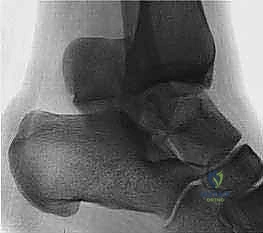

### FIG 3 • Low-energy spiral 43-A type fracture.

24. In contrast to high-energy patterns, rotational injuries ( FIG 3) cause spiral fractures of the distal tibia and fibula originating at the articular level. Intra-articular injury, if present, is typically simple and without comminution or impaction. NATURAL HISTORY